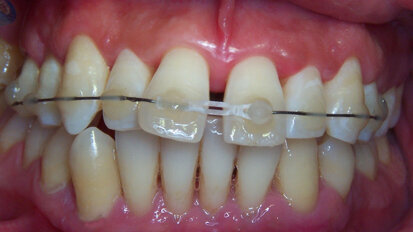

Apprendre à regarder

Des orthodontistes se plaignent du fait que des patients disent qu'ils ne peuvent pas se permettre de traitement dentaire pour des raisons ...